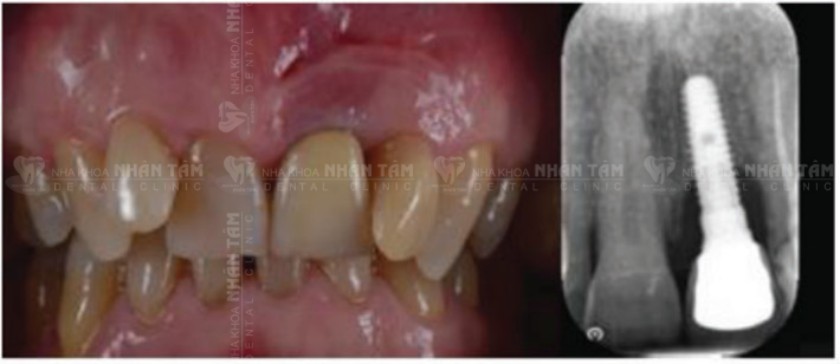

Tình trạng ban đầu: Qua hình ảnh lâm sàng ban đầu và phim chụp X-quang cho thấy túi quanh Implant sâu và tiêu xương ở mức độ vừa phải.

Tình trạng lâm sàng ban đầu và phim X-quang